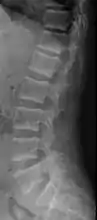

X-ray of a subtle "rugger jersey spine" due to sclerotic bands adjacent to the vertebral endplates.[13]